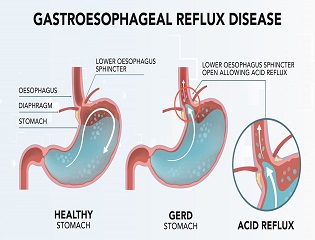

❈ What is Gastroesophageal Reflux Disease (GERD)?

Gastroesophageal reflux occurs when contents in the stomach flow back into the esophagus. This happens when the valve between the stomach and the esophagus, known as the lower esophageal sphincter, does not close properly.

❈ What are the symptoms of Gastroesophageal Reflux Disease?

Common symptoms of gastroesophageal reflux disease are heartburn and/ or acid regurgitation. Heartburn is a burning sensation felt behind the breast bone that occurs when stomach contents irritate the normal lining of the esophagus. Acid regurgitation is the sensation of stomach fluid coming up through the chest which may reach the mouth. Less common symptoms that may also be associated with gastroesophageal reflux include unexplained chest pain, wheezing, sore throat and cough, among others.

❈ What causes Gastroesophageal Reflux Disease?

Gastroesophageal reflux disease (GERD) occurs when there is an imbalance between the normal defense mechanisms of the esophagus and offensive factors such as acid and other digestive juices and enzymes in the stomach. Often, the barrier between the stomach and the esophagus is impaired by weakening of the muscle (lower esophageal sphincter) or the presence of a hiatal hernia, where part of the stomach is displaced into the chest. Hiatal hernias, however, are common and not all people with a hiatal hernia have reflux. A major cause of reflux is obesity whereby increased pressure in the abdomen overcomes the barrier between the stomach and the esophagus. Obesity, pregnancy, smoking, excess alcohol use and consumption of a variety of foods such as coffee, citrus drinks, tomato-based products, chocolate, peppermint and fatty foods may also contribute to reflux symptoms.

❈ How is Gastroesophageal Reflux Disease diagnosed?

When a patient experiences common symptoms of gastroesophageal reflux disease, namely heartburn and/or acid regurgitation, additional tests prior to starting treatment are typically unnecessary. If symptoms do not respond to treatment, or if other symptoms such as weight loss, trouble swallowing or internal bleeding are present, additional testing may be necessary. Upper endoscopy is a test in which a small tube with a light at the end is used to examine the esophagus, stomach and duodenum (the first portion of the small intestine). Before this test, you will receive medications to help you relax and lessen any discomfort you may feel. An upper endoscopy allows your doctor to see the lining of the esophagus and detect any evidence of damage due to GERD. A biopsy of tissue may be done using an instrument similar to tweezers. Obtaining a biopsy does not cause pain or discomfort. Another test, known as pH testing, measures acid in the esophagus and can be done by either attaching a small sensor into the esophagus at the time of endoscopy or by placing a thin, flexible probe into the esophagus that will stay there for 24 hours while acid content is being measured. This information is transmitted to a small recorder that you wear on your belt. X-ray testing has no role in the initial evaluation of individuals with symptoms of reflux disease.

Propping up the head of the bed at night may be helpful.

Should symptoms persist, over-the counter antacids may decrease discomfort. Antacids, however, only work for a short time and for this reason, they have a limited role in treating reflux disease. Histamine H2 receptor antagonists (such as cimetidine, ranitidine, nizatidine, and famotidine) decrease acid production in the stomach. These medications work well for treating mild reflux symptoms and are quite safe, with few side effects. They are available over the counter at a reduced dose, or at a higher dose when given by prescription by your doctor.

Proton pump inhibitors (such as omeprazole, lansoprazole, dexlansoprazole, pantoprazole, esomeprazole, and rabeprazole) are all highly effective in treating reflux symptoms. These medications act by blocking the final step of acid production in the stomach and are typically taken once or twice daily prior to meals. For reflux symptoms that occur frequently, proton pump inhibitors are the most effective medical treatment. These medications typically work well, are safe and have few side effects. There may possibly be an increased risk of certain side effects with high doses or with long-term use (over one year), however. You should discuss this with your doctor if you require long-term use or high doses.

Prokinetics, or medications that stimulate muscle activity in the stomach and esophagus, are sometimes provided for the treatment of reflux disease. The only available drug in the market is metoclopramide, which has little benefit in the treatment of reflux disease and has some side effects, some of which can be serious.

Surgery should be considered in patients with well-documented reflux disease who cannot tolerate medications or continue to have regurgitation as a primary symptom. If symptoms persist despite medical treatment, a comprehensive evaluation should be completed prior to considering surgery. The surgery for treating reflux disease is known as fundoplication. In this procedure, a hiatal hernia, if present, is eliminated and part of the stomach is wrapped around the lower end of the esophagus to strengthen the barrier between the esophagus and the stomach. The operation is typically done via a laparoscope, an instrument that avoids a full incision of the stomach. Due to the complexity of this surgery, it is important to seek a skilled surgeon who has experience in performing this procedure and can discuss the risks and benefits of the procedure.

❈ When should I see my doctor?

You should see your doctor immediately if you have symptoms such as unexplained weight loss, trouble swallowing or internal bleeding in addition to heartburn and/or acid regurgitation. Symptoms that persist after you have made simple lifestyle changes also warrant a visit to your doctor. In addition, if you use over-the-counter medications regularly to reduce symptoms such as heartburn or acid regurgitation, you should consult a physician to determine the best course of treatment for you.